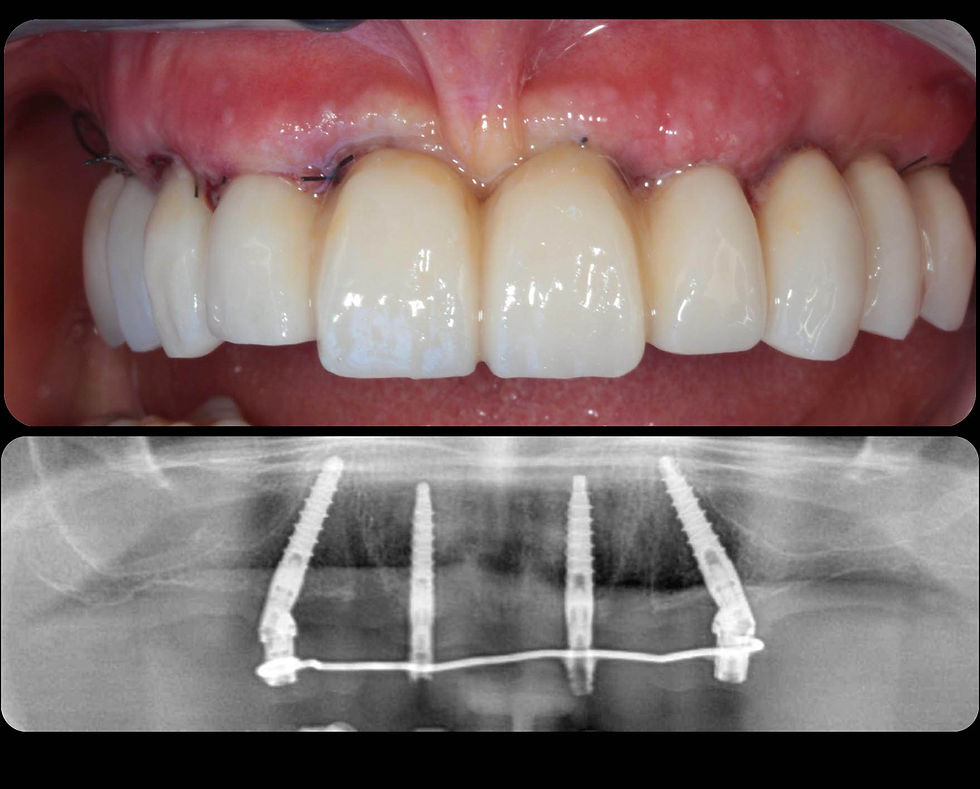

The “Simple” temporary restoration delivered within 24 hours and the related radiographic control.

Comparison between the immediate post-operative radiographs and the 4-years follow up radiograph. Note the complete stability of the crestal bone, even in the most difficult position, around the tilted distal implant. Signs of neo-corticalization are visible, which are very frequent according to our experience with Prama implants.